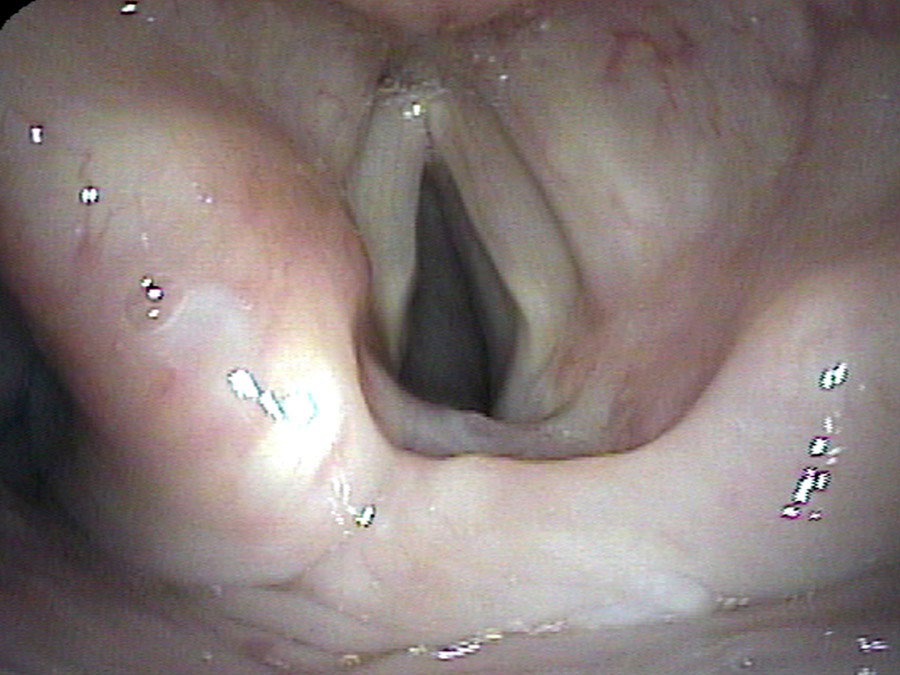

Mrs. A. Gris did just fine for five years. She again developed pain in her neck and found a new neurosurgeon who chose to approach the neck from the opposite side. Perhaps he heard her good voice and assumed that her vocal cords were working normally. She awoke from this second neck surgery with no voice again. Over a few weeks her voice started to return, but it was still weak when I first saw her. The right vocal cord, previously injured, was seen to be in a nearly fixed position near the midline. The left vocal cord, newly injured, could move slightly apart with breathing in.

Unfortunately, the regrowth of the injured RLN, while very helpful in a one-sided injury, usually becomes a significant problem when the same regrowth happens on the second side. Over the next several months, her voice did indeed become stronger as the nerve grew back. Breathing also became more difficult. When she would actively breathe in, the recently injured left cord would actively close. Enough of the fibers that normally opened her vocal cords during inspiration (via the PCA muscle) had grown into the muscle that closes the vocal cords for speaking (LCA muscle) such that, the deeper she breathed in, the more strongly the left cord closed.